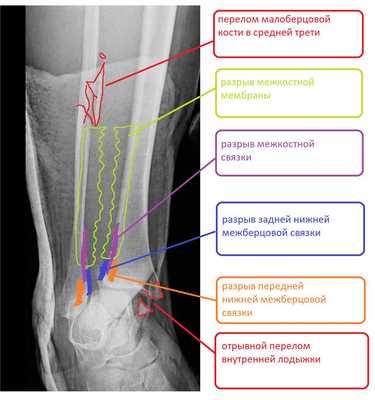

Пациент Д.27 лет, травма в результате неудачного приземления после прыжка старзанки на мелководье. Стопа ушла кнаружи относительно фиксированной голени. Произошёл перелом малоберцовой кости в средней трети с разрывом всех компонентов дистального межберцового синдесмоза и отрывной перелом внутренней лодыжки.

Данный тип переломов лодыжек считается очень тяжёлым и относится к категории 44С2 по классификации Ассоциации Остеосинтеза. Казалось бы, сломаны всего 2 кости, да и переломы по своей морфологии не особо и тяжёлые, почему же данный тип переломов лодыжек считается крайне тяжёлым?

Всё дело в повреждении мягких тканей, прежде всего разрыве всех 4 компонентов дистального межберцового синдесмоза - передней и задней нижних межберцовых связок, межкостной связки и межкостной мембраны. Вместе с отрывом медиальной лодыжки всё это делает перелом абсолютно нестабильным и требует операции в 100% случаев.